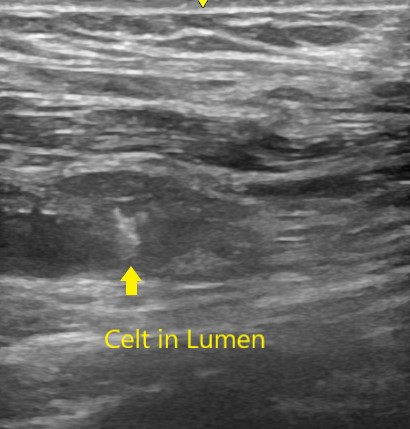

I use a closure device for all femoral access.7 Closure of the artery requires specific attention to detail, and its importance should not be minimized, particularly in the OBL environment. The operator should be intimately involved with this process. My closure device of choice Is the Celt ACD vascular closure device (Veryan Medical).8 It can be visualized under both ultrasound and fluoroscopy, gives a secure closure, and works well in the presence of arterial calcification. The Celt ACD vascular closure device requires sufficient training and experience to utilize effectively (Figure 1A-B).